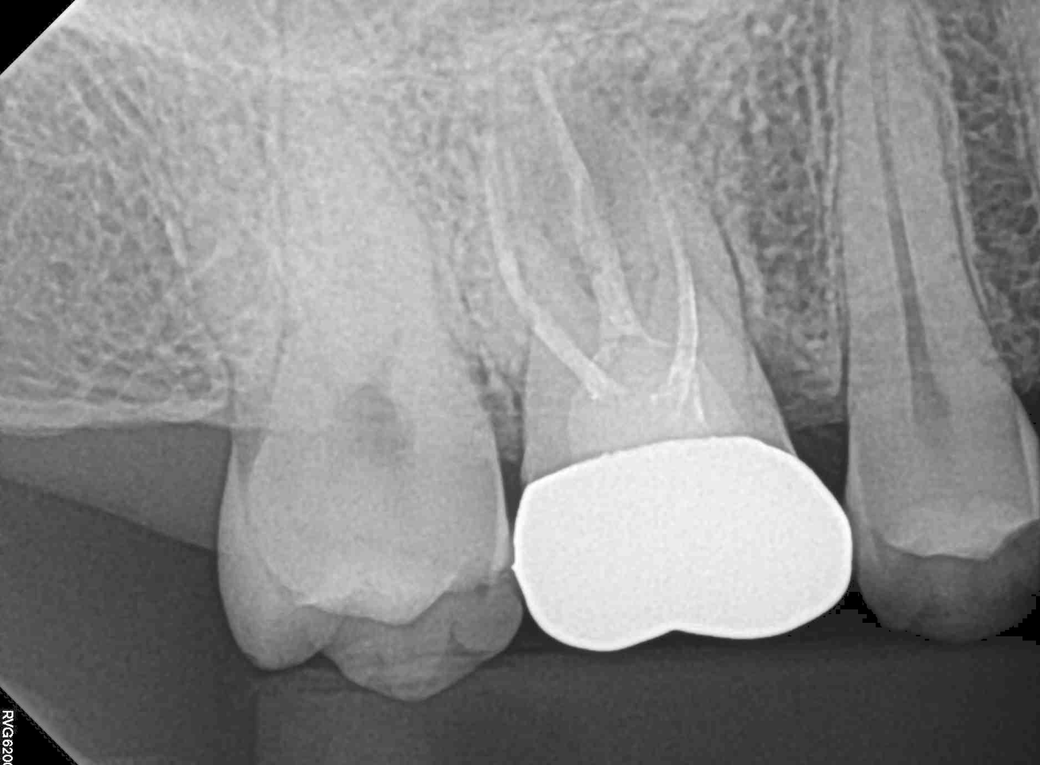

2. 두 치과 모두 뿌리염증이 있다고만 하고 어느 정도인지는 구체적으로 설명을 안 해줬습니다. 사진 상으로 어떤 정도인지 궁금합니다(비교용으로 그간 찍었던 사진을 같이 첨부했습니다) 최근 파노라마를 보면 오른쪽 신경 옆쪽으로 약간 검은 음영이 있는데 이게 뿌리 염증일까요?

그리고 최근 치근단 사진을 보면 신경에서 하얗게 치료된 부분 위로 검은 부분이 보이는데 신경치료가 완전하게 되지 않은 게 맞을까요?

2022년 8월 치근단

23년 6월 파노라마, 치근단

• 1번 째 사진

• 2번 째 사진

• 3번 째 사진

• 4번 째 사진

• 5번 째 사진

• 6번 째 사진

-사진상으로 보면 재신경치료를 하시는것보다는 발치를 해야될 가능성이 높아 보이네요.